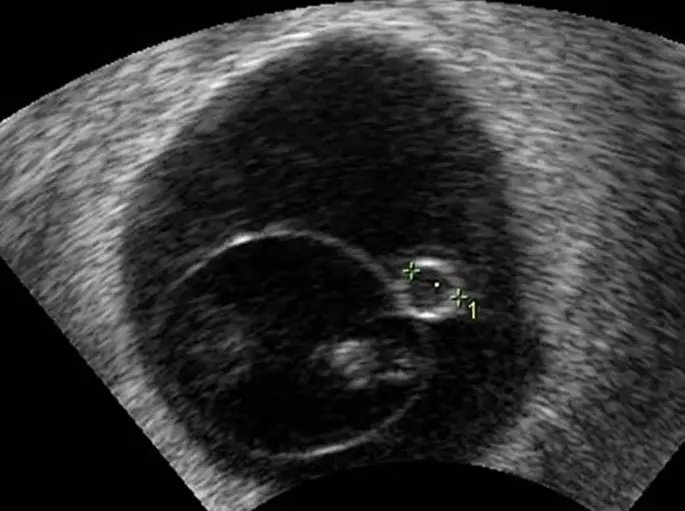

In der Schwangerschaftswoche sollte die Fruchthöhle einen Durchmesser von etwa 10-15 mm haben. In dieser Woche kann der Embryo bereits sichtbar sein und sollte etwa 3-5 mm groß sein. Der Dottersack, der dem Embryo Nährstoffe liefert, sollte außerhalb der Amnionhöhle liegen und einen Durchmesser von etwa 5 mm haben.

Der Dottersack ist eine kleine, runde Struktur, die sich innerhalb der Fruchthöhle befindet. Er liefert dem Embryo in den ersten Wochen der Schwangerschaft Nährstoffe und Sauerstoff. Der Dottersack schrumpft mit der Zeit, wenn die Plazenta beginnt, die Rolle der Nährstoffversorgung zu übernehmen.

Die Größe der Fruchthöhle wird mit einem Ultraschall gemessen. Der Arzt kann die Größe der Fruchthöhle anhand des Ultraschallbildes messen.